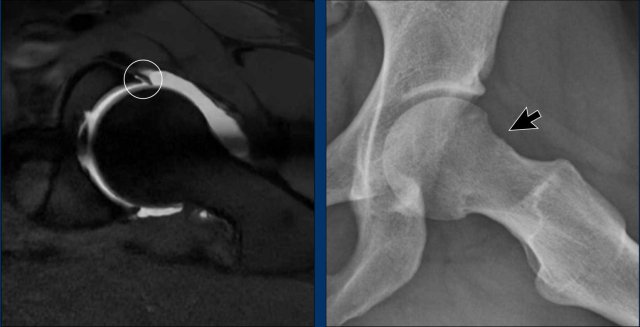

Combination of Cam and Pincer morphology

These images are from a 28-year-old woman who participates in CrossFit at a professional level. She has been experiencing complaints in the left hip region, specifically on the anterior side, for the past year. The symptoms worsen during squats and hip flexion.

Upon examination, there is reduced hip flexion (painful at 120°) and limited rotation (restricted to 20° and painful).

First study the radiograph.

Then continue with the detailed views...

Although the findings are subtle, there is evidence of Pincer morphology, indicated by the crossover sign and ischial spine sign.

The retroversion of the acetabulum results in increased prominence of the ischial spine and leads to the superior portion of the anterior wall of the acetabulum overlapping the posterior wall on imaging.

Furthermore, there is a mild indication of Cam morphology.

Continue with the MR-arthrogram...

Subsequently, MR arthrography was performed, revealing a labral tear in the anterosuperior region.

Initially, the patient was treated conservatively with physiotherapy, but this did not lead to satisfactory results.

An arthroscopic procedure was then performed, involving a reshaping of the femoral head-neck junction (arrow), which resulted in significant improvement.